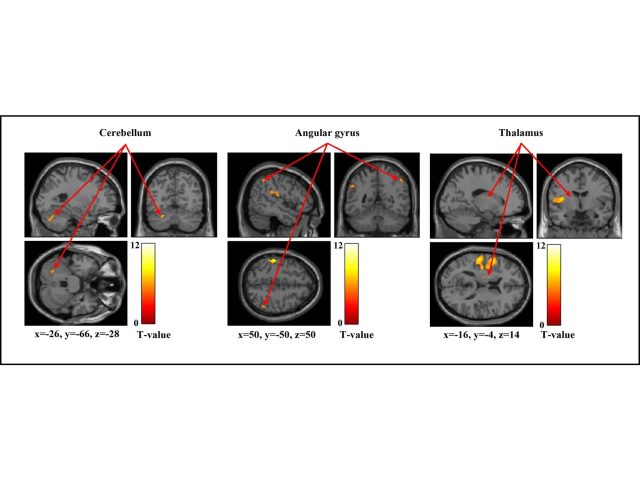

新潟医療福祉大学大学院(放射線情報学分野)・川村瞭さんらの研究グループは、強さの異なる機械的刺激に対して脳がどのように反応するかを調べました。その結果、刺激が強くなるほど脳の賦活が高次の領域へ広がることが分かりました。また、痛みの感受性の違いによって、刺激に対する脳内処理が異なる可能性が示されました。

本研究は複数の強度による機械的刺激を与えた際の脳賦活部位を特定しました。また、刺激に対する脳賦活と疼痛閾値との関連について検討しました。結果から、刺激強度の増加に伴って高次領域に賦活が拡大すること、疼痛閾値の違いが刺激に対する脳内処理の違いを反映している可能性が明らかになりました。

・複数の刺激強度で機械的刺激を与えた際の脳賦活部位を特定しました。